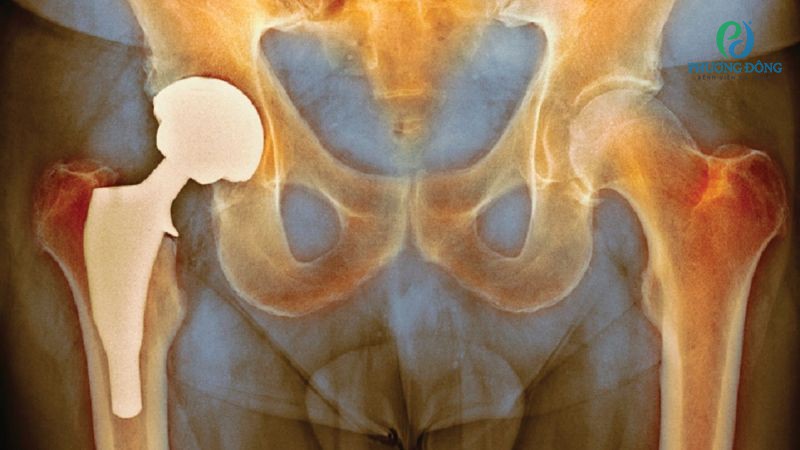

Dựa vào thời gian khởi phát, có thể phân loại độ nhiễm trùng hậu can thiệp thay khớp háng như sau:

- Giai đoạn 1 xảy ra rất sớm, chỉ trong vòng 6 tháng sau phẫu thuật.

- Giai đoạn 2 xuất hiện muộn hơn, gây viêm sau mổ thay khớp háng từ 6 - 12 tháng.

- Giai đoạn 3 được xác định lây nhiễm vi khuẩn qua đường máu từ bộ phận khác trong cơ thể, xảy ra sau 2 năm kể từ khi thay khớp.

Phân loại biến chứng nhiễm trùng dựa vào thời gian khởi phát